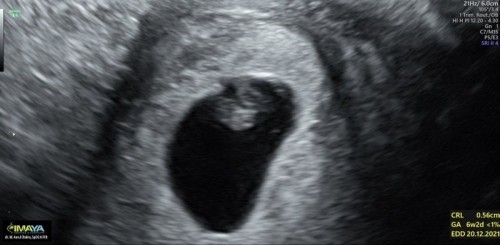

HPHT 16 Februari, usg hari ini GA 6w, CRL 0.56cm. Belum kedengeran denyut jantung. Normal kah???

Bunda-bunda.. aku lagi down nih.. ini kehamilan pertama, setelah menanti 2.5th. Jarak mens tiap bulan 30-35 hari, 2x jarak 40hari Aku HPHT 16 Februari 2021 Usg pertama, tgl 12 April, GA 8w, GS 2.93, CRL blom ada Usg kedua, tgl 28 april, GA 6w, CRL 0.56cm Dan belom kedengeran denyut jantung. Bingung bunda. Kata dokter suruh balik lagi minggu depan. Apa bener GA bisa berubah karna jarak haid lama?? Kok bisa yaaa dari 8w, langsung ke 6w??#seriusnanya #bantusharing #ingintahu #jangandibully #firstbaby Sedih, bimbang bunda 😭😭 Adakah yang sama kaya saya???